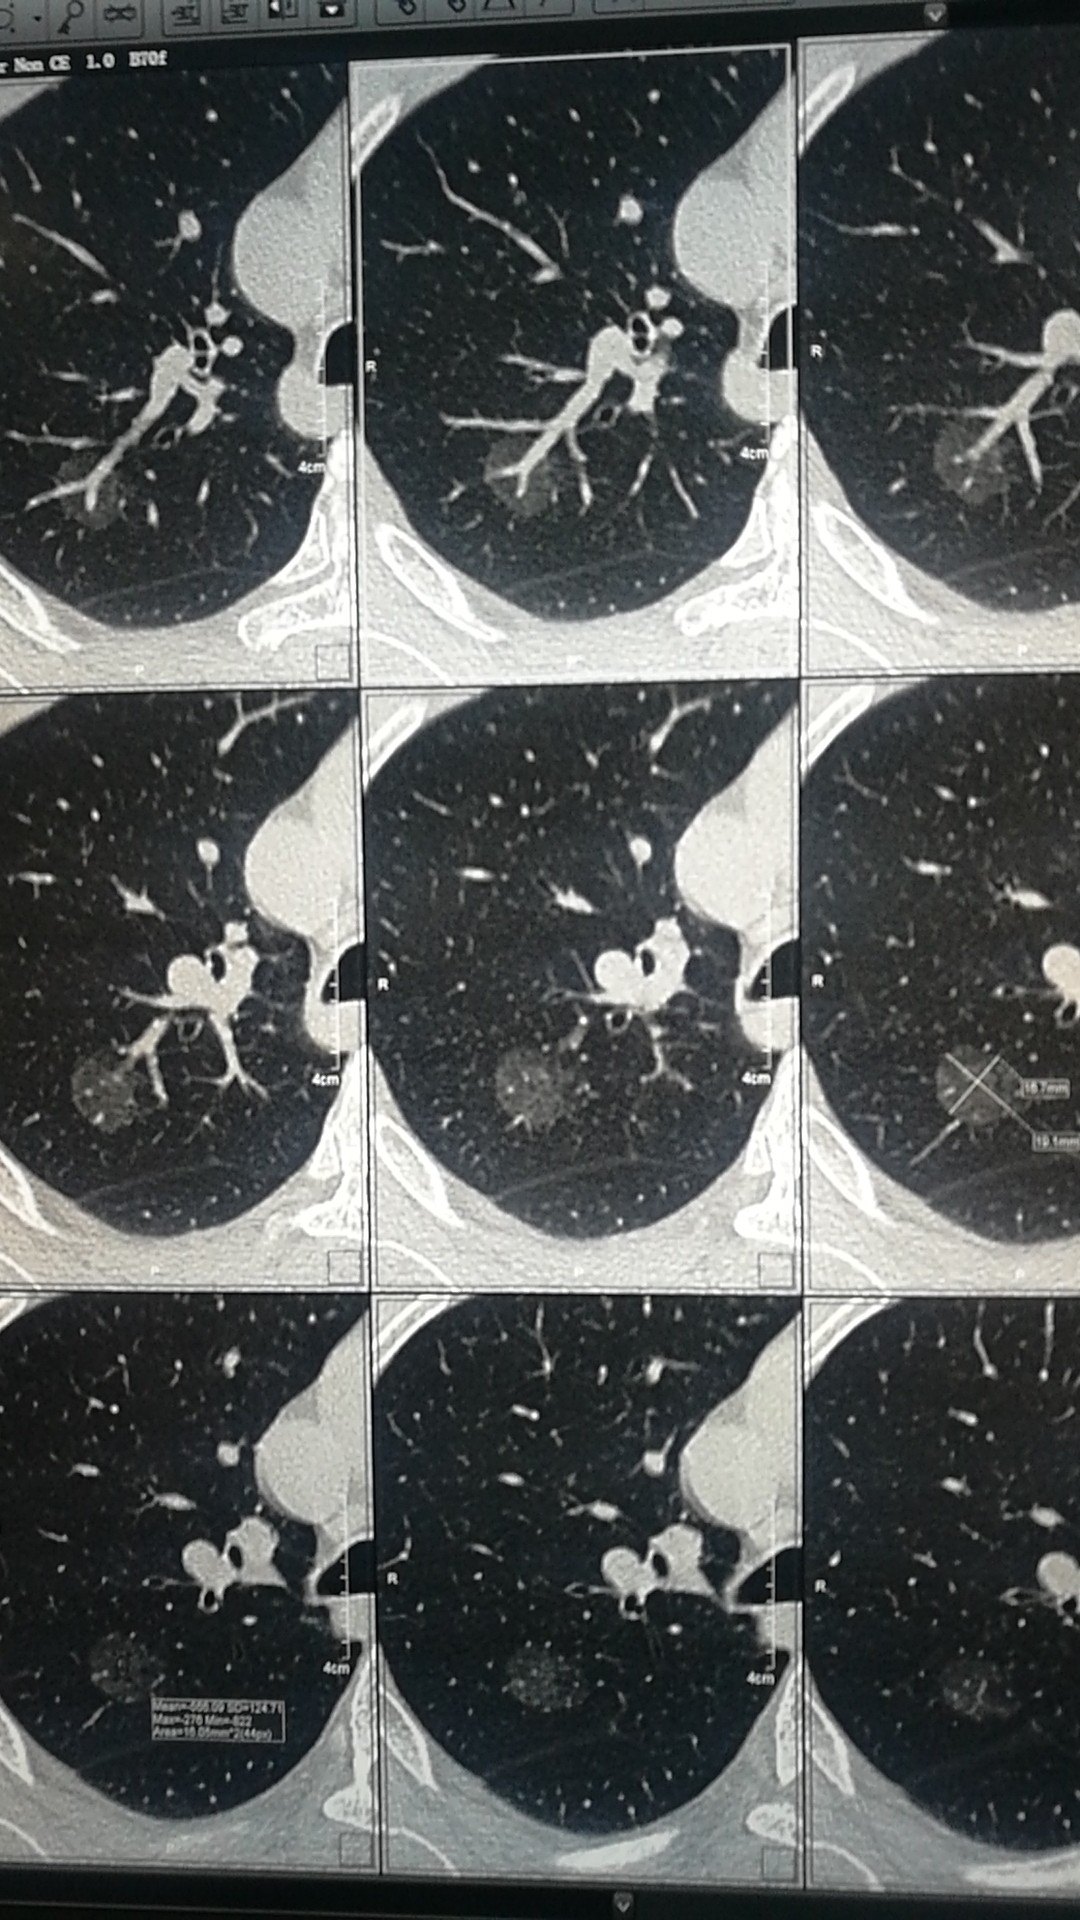

【影像读片】右肺磨玻璃影 [病例帖]

右下肺见8mmx9mm磨玻璃密度结节